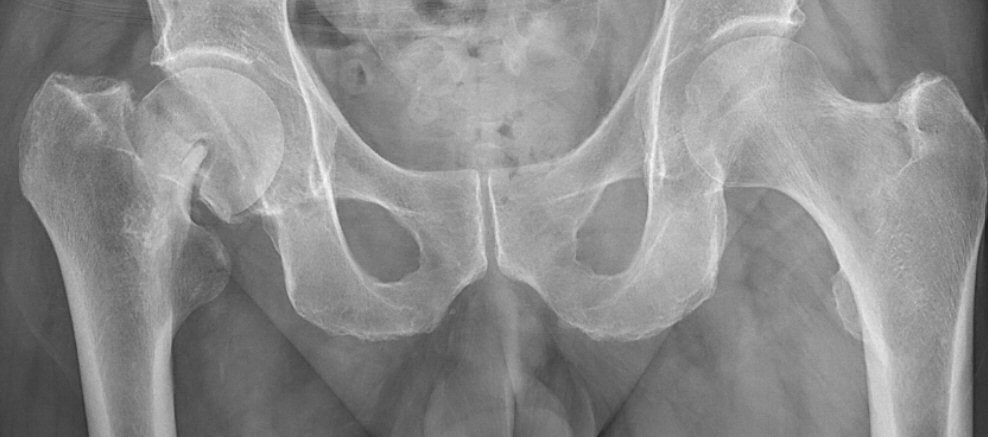

- Värdera om röntgenbilden är tagen rakt framifrån. I så fall bör coccyx och symfysen ligga över varandra och foramina obturatoria bör vara symmetriska.

Första bilden är nästan rak frontal med överlappande coccyx och symfys samt symmetriska foramina obturatoria. Andra bilden är inte rak.